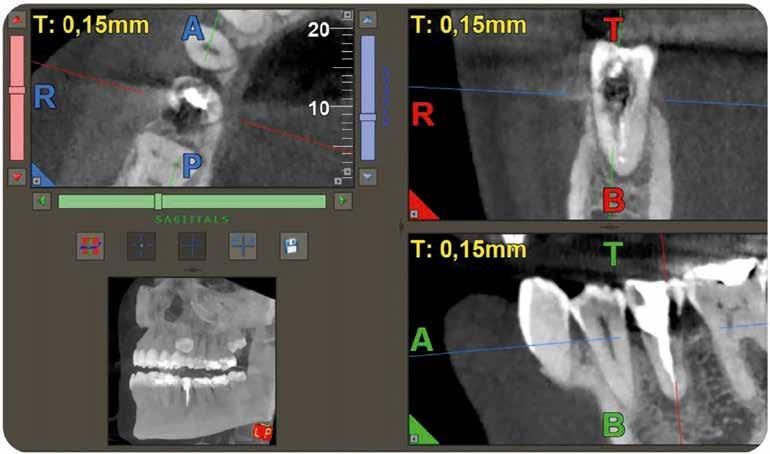

A radiológiai felvételek elemzése során a fog gyökércsúcsának megfelelően radiolucens elváltozást észleltünk, valamint a fognyak területének megfelelően szintén egy radiolucens területet figyelhettünk meg (1–2. ábra). Az elváltozások kiterjedésének és mélységének pontosabb meghatározása érdekében CBCT-felvétel készült (3. ábra). A felvétel alapján Heithersay-féle III. osztályú külső fognyaki gyökérfelszívódást diagnosztizáltunk (Heithersay Class III external cervical invasive root resorption; ECIR). Ezzel egyidejűleg pedig szimptomatikus periapikális periodontitis is fennállt. Ezt követően a pácienst a vizsgálati eredményekről, a kezelési alternatívákról és a várható prognózisról is tájékoztattuk.

A CBCT-felvételek rendkívül hasznos információkkal szolgálhatnak az endodonciai kezelések során. A felvételek segítségével meghatározhatjuk a külső fognyaki rezorptív lézió kiterjedését, felismerhetjük és osztályba sorolhatjuk az esetleges periapikális elváltozásokat, valamint nagyobb pontossággal felmérhetjük a fog belső anatómiai felépítését. Több szerző egymástól függetlenül is igazolta, hogy a CBCT rendkívül hasznos eszköz a rezorptív léziók diagnosztizálása során.

3. a–d ábra: A koronális síkú metszeten jól megfigyelhető a lézió mesio-distalis kiterjedése (a), a szaggitális síkú metszet a lézió vesztibulo-orális nagyságát mutatja (b), a gyökércsúcs körül elhelyezkedő lézió a 3 dimenziós rekonstrukciós képen és a mesio-disztális irányú metszeten is jól megfigyelhető (c–d).

A cikkekben bemutatott esetnél a kezelésre szoruló fog gyökércsúcsánál periapikális lézió volt megfigyelhető és ezzel egyidejűleg külső fognyaki gyökérrezorpció is fennállt. A periapikális és a rezorptív lézió méretének pontos meghatározását és térbeli elhelyezkedésének vizsgálatát CBCT-felvétel segítségével végeztük.